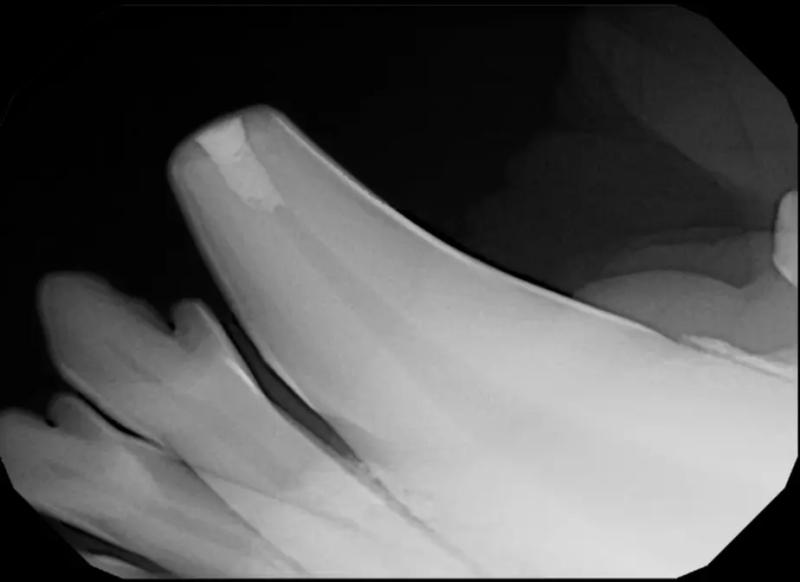

Root canal therapy is an excellent option for saving important teeth that have been fractured or are determined to be non-vital. The procedure is performed exactly as it would be for a human, except your pet will be dreaming peacefully under anesthesia. In many cases, root canal therapy is much easier on your pet than extraction, and preserves the structure of the tooth. It is important to have the root canal x-rayed periodically to monitor for any problems.

Periodontal disease is extremely common in dogs and cats. Over 80% of dogs and cats over two years of age have some degree of periodontal disease. Periodontal disease is best prevented by yearly professional dental cleanings starting at two years of age and at home brushing at least three times weekly. Brushing should begin at a very early age to allow your new pet to get used to regular brushing. In severe cases of infection or periodontal disease, the teeth may need to be surgically extracted. Extractions should always involve x-rays of the tooth first, as many teeth have multiple roots or may be diseased below where the eye can see. Extracting larger teeth in animals requires oral surgery, equivalent to removing wisdom teeth in people. It is vital that all of the tooth and roots be removed for the periodontal infection to resolve. In cases of important teeth with mild to moderate periodontal disease, multiple periodontal treatments can be offered to help save these teeth.

Pets can be involved in trauma that can cause fractures to their head, teeth, and jaw bones. Correctly repairing these fractures is extremely important for your pet to have normal function of their mouth. If a jaw fracture is allowed to heal in an abnormal position, your pet may have great difficulty chewing and can be in significant pain. Many fractures can be successfully treated with minimally invasive oral procedures, but more complicated cases may require bone plating techniques. The Center offers cone beam CT imaging which provides extremely detailed images of the bones of the head and skull. Advanced imaging with CBCT facilitates selection of the best surgical technique to get your pet back to eating and comfort as soon as possible.